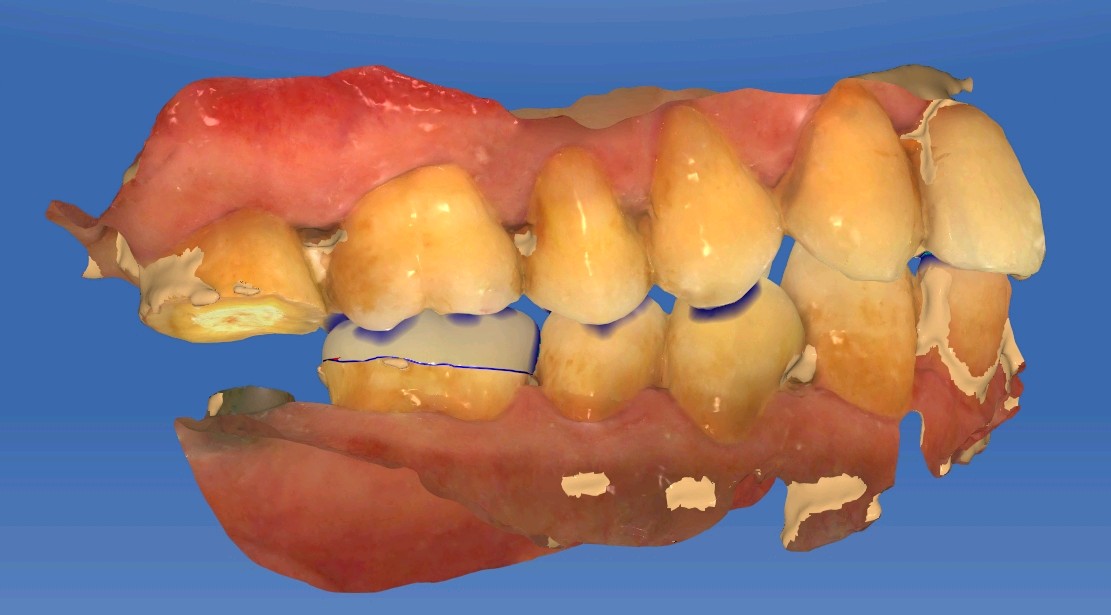

患者男,五十岁,右下后牙咬合不适,前来外院就诊。X线片显示46根尖部有阴影。口内检查发现,颌面大面积树脂充填物,周边有继发性龋坏。探-,叩+,余无不适。治疗计划:根管治疗后高嵌体修复。

补牙在操作过程中很容易受到唾液污染、口腔空间较小等因素影响粘结效果,长期磨耗容易脱落缺损。从而进一步引发继发龋。基牙很容易受损。根管治疗后的牙齿可以选择高嵌体和牙冠修复。这位患者牙体缺损不是较少,所以建议高嵌体修复。先用数字化口扫技术扫描患者口腔内备好的牙体形态,在口外模型上由专业技师制作出来,最后再由医生将嵌体粘固在缺损的牙齿上修复,因此治疗过程一般需要1-2次。更精细,密合度高,修复后牙缝不易塞牙 更好恢复咀嚼功能,窝沟点隙也更加清晰。

术前

术中

术后